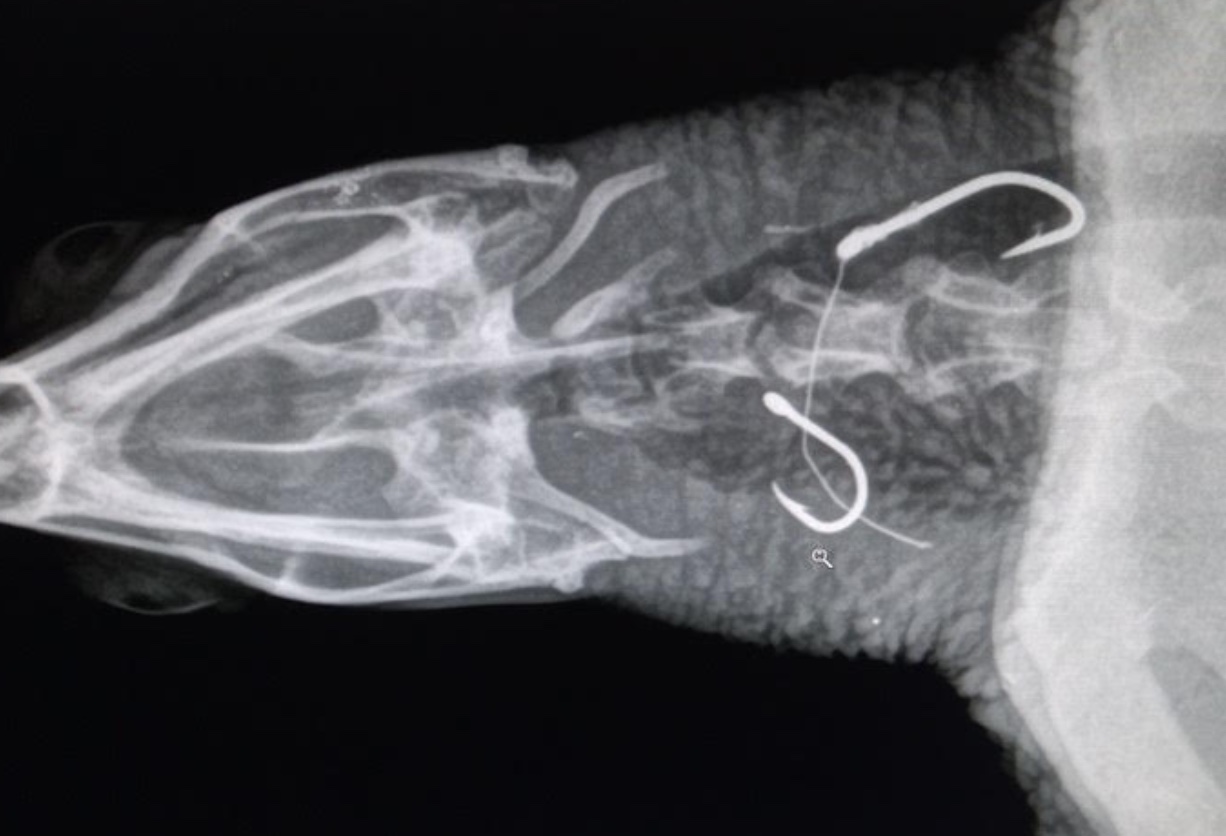

Des radios ont été réalisées lundi matin pour localiser les hameçons et déterminer le mode opératoire pour les retirer.

L’une des trois tortues avait avalé trois hameçons: un dans l’oesophage, un dans la partie distale de l’intestin, et un dans la trachée.

Cela montre que les hameçons se déplacent dans le corps de la tortue avec des conséquences parfois réduites, si ils suivent le transit intestinal - mais aussi plus graves lorsque les hameçons atteignent des organes sensibles, comme cela est le cas pour la trachée.

Un autre risque important lors de captures accidentelles, est l’enchevêtrement dans le fils de pêche qui reste attaché à l’hameçon. Cela peut provoquer un étranglement ou des amputations des nageoires. D’où l’importance d’intervenir le plus rapidement possible aprés que l’hameçon ai été avalés.